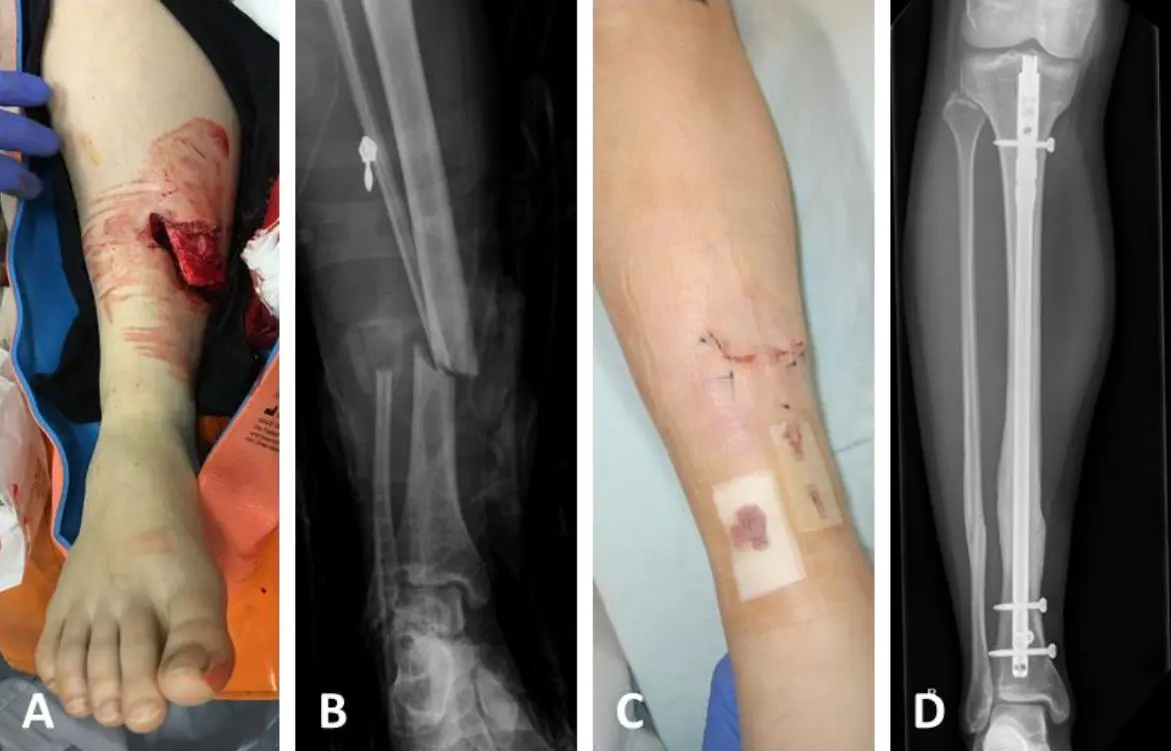

Bei einem komplexen Armbruch, der mehrere Knochenstücke betrifft, oder bei einem verschobenen Bruch, kann eine operative Behandlung erforderlich sein. Die operative Behandlung umfasst in der Regel:

- Fixierung des Bruchs: Der Bruch wird mit Schrauben, Platten oder Drähten fixiert.

Externe Fixation

Bei dieser Methode werden Stifte und Schrauben in den Knochen eingeführt und mit einer externen Stange verbunden. Diese Methode wird häufig bei Brüchen eingesetzt, bei denen die Weichteile stark verletzt sind.